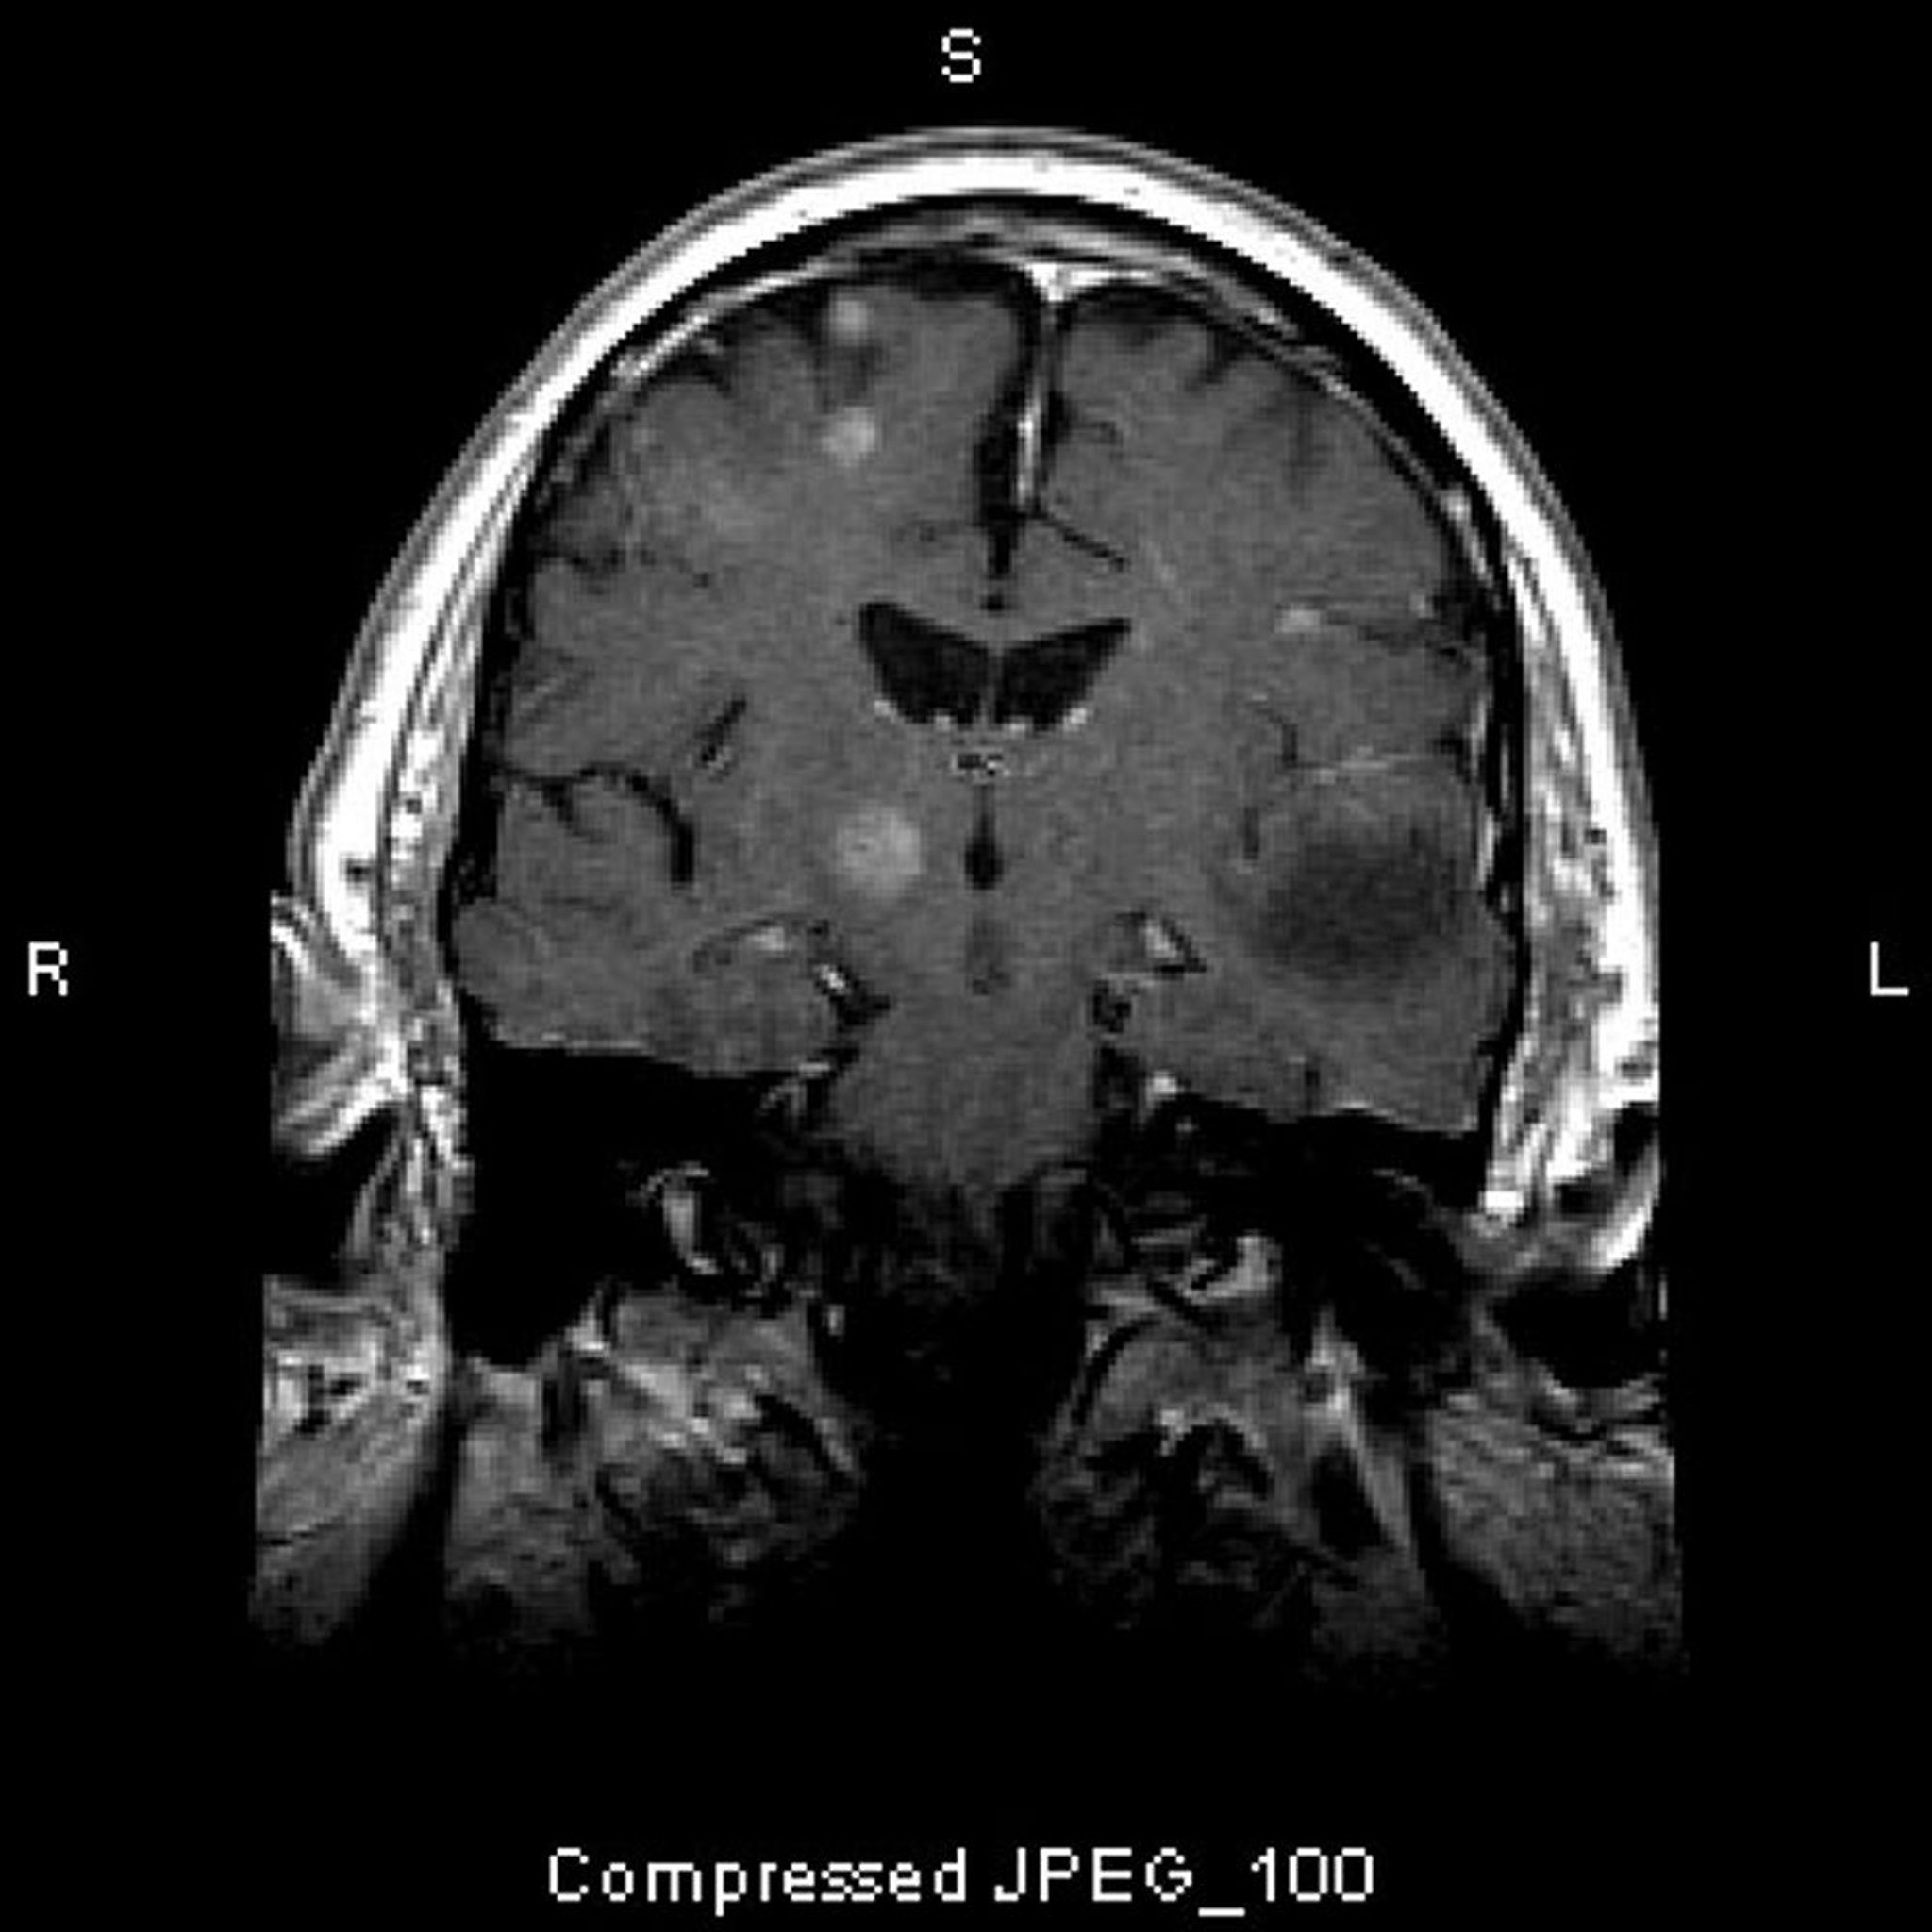

Diagnosi dei tumori endocranici

• RM pesate in T1 con gadolinio o TC con mezzo di contrasto

• Talvolta biopsia

Si deve effettuare un esame neurologico completo, uno studio di neuroimaging, e RX torace (per la ricerca di fonti metastatiche). La RM con sequenze pesate in T1 con gadolinio è lo studio di scelta. La TC con mezzo di contrasto è un'alternativa. La RM rivela solitamente astrocitomi a basso grado di malignità e oligodendrogliomi più precocemente rispetto alla TC e mostra più chiaramente le strutture cerebrali in prossimità dell'osso (p. es., fossa cranica posteriore). Qualora gli esami di diagnostica per immagini dell'encefalo non siano sufficienti a mostrare nel dettaglio la zona di interesse (p. es., sella turcica, angolo pontocerebellare, nervo ottico), si devono eseguire indagini neuroradiologiche più dettagliate dal punto di vista spaziale o altre particolari proiezioni dell'area interessata. Se si sospetta un'ipertensione endocranica in presenza di uno studio di neuroimaging normale, deve essere considerata un'eventuale ipertensione endocranica idiopatica e bisogna eseguire una puntura lombare.

Gli indizi riguardo al tipo di tumore, principalmente la sua localizzazione clinicamente sospettata (vedi tabella Manifestazioni localizzanti comuni dei tumori al cervello) e il tipo di enhancement alla RM, possono essere non dirimenti; la biopsia cerebrale e talvolta una biopsia escissionale possono essere necessarie.

Dopo la radioterapia diffusa o panencefalica, molti bambini e adulti sviluppano neurotossicità ritardata-tardiva se sopravvivono abbastanza a lungo. La causa più frequente nei bambini è la radioterapia diffusa per prevenire la leucemia o per trattare il medulloblastoma. Dopo la terapia diffusa, il sintomo più comune è la demenza progressiva; gli adulti possono anche sviluppare un'andatura instabile e sintomi neurologici focali. La RM o la TC possono mostrare atrofia cerebrale e spesso perdite di sostanza bianca.

La RM o la TC mostrano una massa che può essere potenziata dal mezzo di contrasto e che può essere difficile da distinguere da una recidiva del tumore primario. La biopsia escissionale della massa è diagnostica e spesso migliora la sintomatologia.